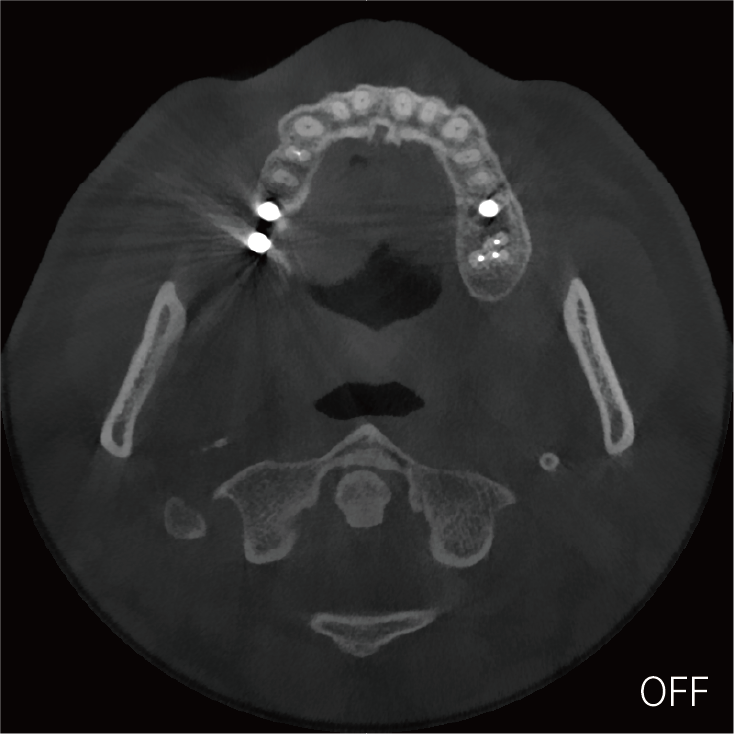

超能去伪 至臻影像

临床样片